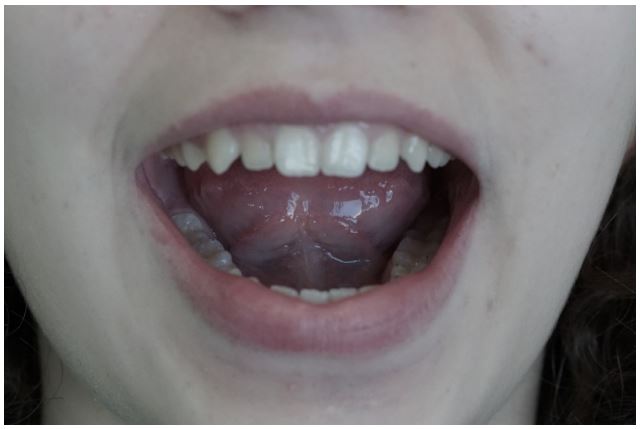

On presentation, the patient had a panoramic radiograph, where the TMJ depicted rather atypical (Figure 4). The diagnostic process could not rely on this x-ray, due to the overlaps with other anatomical elements in the region; this additional imaging techniques deemed necessary [14]. The Cone beam computed tomography (CBCT) which was selected in this instance, revealed on the right side that the condyle was centrally positioned, while erosive lesions were seen in the upper anterior region of the condyle at the medial pole. Microerosions at the outer pole could not be ruled out. Early to moderate degenerative alterations were consistent with this image (Figure 5).

Figure 4: The panoramic X-ray is a diagnostic imaging technique used in dentistry that provides a broad angle of the teeth and jaws. Both sides of the TMJ are also depicted. Atypical morphology can be noticed in the temporomandibular joints, despite their potential overlap with other anatomical structures.